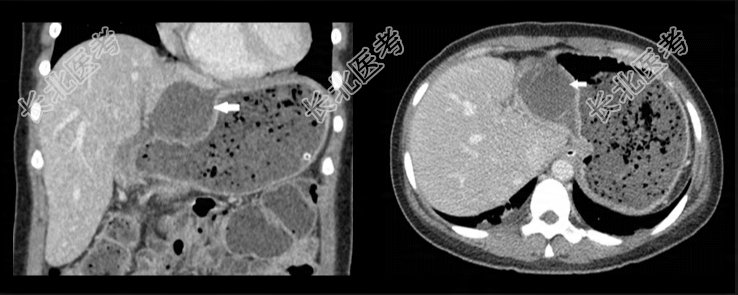

入院12h,患者自述腹痛加剧伴发热,腹部检查示右上腹压痛和肌卫,墨菲氏征阴性。实验室检查显示白细胞计数升高(13,300/μL),中性粒细胞占比86%。腹部CT检查显示胆囊体和底部从胆囊窝移位至肝胃隐窝,胆囊明显肿胀伴胆囊壁弥漫性增厚,无不透光结石,胆囊壁增强减弱。基于上述发现,诊断为胆囊扭转伴急性非结石性胆囊炎。